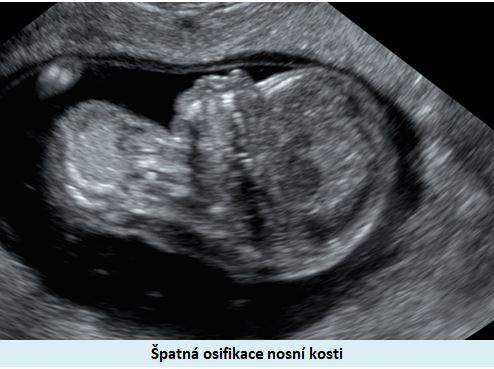

Ultrazvuková diagnostika se při screeningu v 1. trimestru opírá o šířku podkoží v záhlaví plodu, osifikaci nosní kůstky a nálezu abnormálních průtoků v srdci plodu (trikuspidální regurgitace, reversní tok v ductus venosus).

Pracoviště se zkušenostmi v prenatální diagnostice a s dobrým přístrojovým vybavením je schopno vyslovit podezření na tento syndrom ve více jak 90% případů již při ultrazvukovém vyšetření ve 12-13. týdnu těhotenství. .